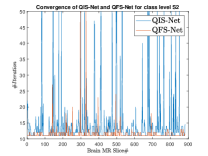

where, represents the true interconnection weight terms of the inter-connection weights as expressed using the Hadamard gate () at an instance (). is a coherent error function of and . Convergence analysis of the proposed qutrit-inspired QFS-Net is provided in Appendix Section -A and demonstrated experimentally with qubit embedded QIS-Net [39] as shown in Figure 3. It can be summarized that the convergence of the QFS-Net is faster than that of the QIS-Net and also follows super-linearity. This claim is also substantiated by the number of iterations required to converge for each image slice in QFS-Net and QIS-Net as illustrated in Figure 4.